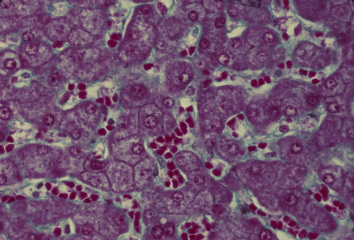

肝臓 18. 肝細胞索と類洞.

ヒト、ブアン液で固定、パラフィン包埋、マッソン-ゴールドナー(M-G)染色、x 160.

M-G染色では細網繊維を青緑色に,肝細胞を赤く、赤血球を赤橙色に

染め分けるので、肝細胞索と類洞とを明瞭に識別できる。この図では、

類洞の中に赤橙色に染まった赤血球が適当に含まれているので、類洞が

特に明らかである。肝細胞索では、胆毛細管がここかしこで観察される。

Liver 18. Hepatic cell cords and sinusoids.

Human, fixation with Bouin's fluid, embedding with paraffin, M-G stain, x 160.

As M-G stain stains reticular fibers bluish green, hepatic cells

red and erythrocytes reddish orange, we can easily distinguish

hepatic cell cords from sinusoids. As in this preparation sinusoids

contain properly erythrocytes, sinusoids are especially clear.

Among the hepatic cell cords bile canaliculi are seen here and there.